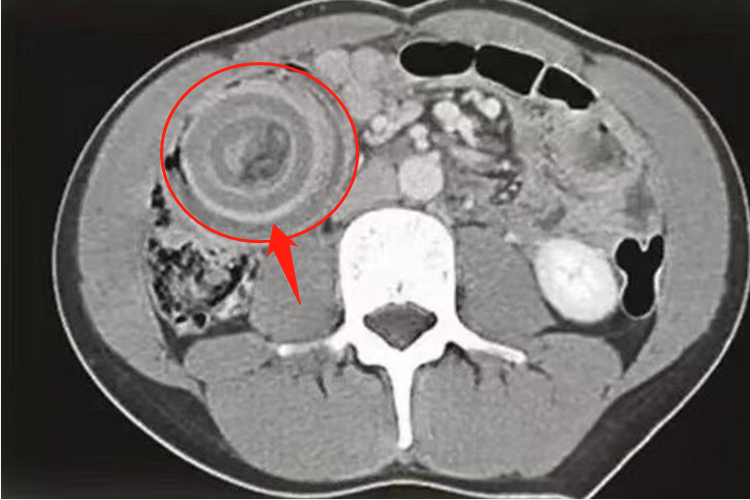

对于出现肠套叠的患者,CT检查常表现为腹腔内软组织肿块影,肿块呈高低密度相间的分层状或环状,分别代表套入部肠腔、肠壁、肠系膜脂肪及鞘部肠腔和肠壁,靶心为套入部的肠腔,其周高密度环为肠壁。增强扫描肠壁有明显强化。口服造影剂进入套入部,则靶心密度很高,CT表现以套入的肠系膜脂肪形成新月形或半环形的脂肪密度区最具有诊断特征。